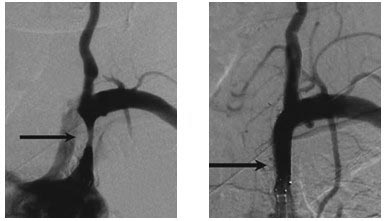

典型病例二:

患者,男,68岁,因“右侧肢体偏瘫”入院,DSA提示左侧大脑中动脉重度狭窄,予以支架置入治疗。术后随访1.5年,患者脑梗塞无复发。

治疗前 治疗后